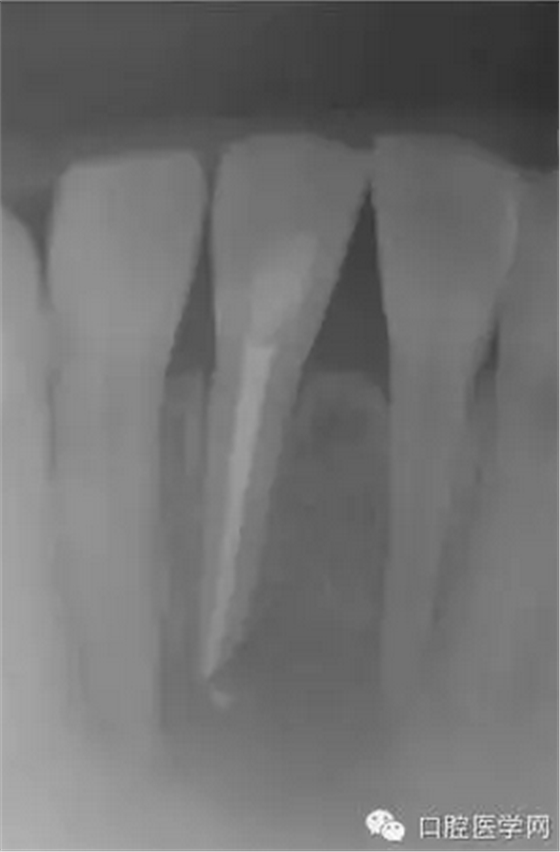

(圖 3) 根管充填

2天后讓患者復(fù)診,查看根管狀態(tài),發(fā)現(xiàn)根管內(nèi)依然有膿液流出,用注射器和針管將根管內(nèi)的膿液吸出來,使用生理鹽水清洗根管后,再用棉球?qū)⒏芊夂谩?天后復(fù)診時,根管狀態(tài)大有好轉(zhuǎn),用NaOCl溶液清洗根管后,為防止根管污染,開髓口使用氧化鋅密封。第10天,切口部位基本痊愈,腫脹也完全消失。此后每隔1~2周復(fù)診一次,使用NaOCl溶液清洗根管,根管內(nèi)填充水溶性氫氧化鈣糊劑。從開始治療算起,約2個月后,不再有癥狀,進(jìn)行根管充填。